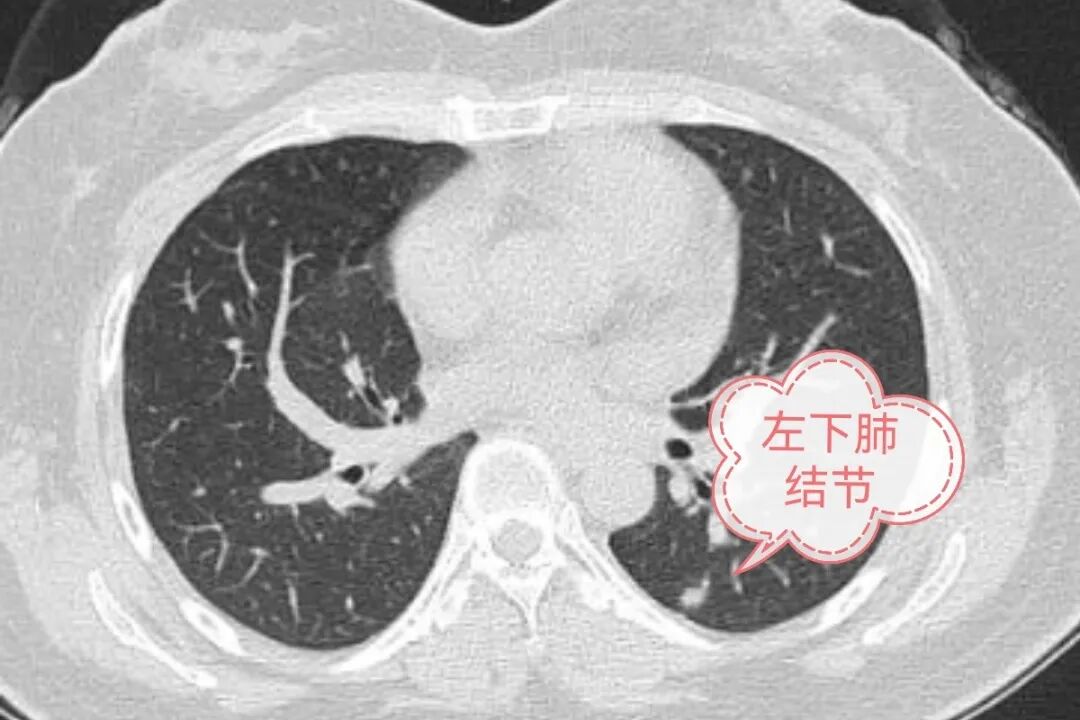

“手术一结束,我就醒过来了,当时就感觉喉咙和胸口没有第一次手术时那么难受。医生把我推回病房时,我自己就能从推车走到病床躺下,而上次是需要被抬过去的。更让我意外的是,这次身上没有插引流管和尿管,感觉比第一次手术轻松太多了!。”近日,在贵州航天医院心胸外科接受了第二次肺结节手术的王女士(化名)说道。 案例分享 这已是王女士两年内的第二次肺结节手术。去年,她体检发现右肺和左肺各有一个磨玻璃结节,右肺结节(活检提示肺腺癌)接受了双腔气管插管全麻单孔胸腔镜手术,尽管手术成功,但术后的不适让她记忆犹新。 今年10月复查时,发现左肺的结节比一年前密度增高,早期肺癌可能性大,需要再次手术。心胸外科陈光春教授团队为她实施了“无管”手术——一种不插气管插管的全身麻醉方式,用喉罩辅助并在术中保留她的自主呼吸。 让王女士意外的是,这次从苏醒、下床活动到出院,整个体验都“轻松太多了”——术后第一天可下床活动,三天便出院了。 技术科普 “无管”手术又称Tubeless技术,顾名思义,就是在手术过程中和术后,患者身上不插或只插较少的管子,是一种更微创、更注重患者舒适度的手术方式。 “ 可以这样理解 (一)关于“怎么呼吸” ※传统手术:需要在喉咙里插入一根较粗的呼吸管,靠呼吸机来帮助肺工作。这根管子可能会让喉咙不舒服,术后容易感觉喉咙痛、咳嗽。 气管插管 ※“无管”手术:不需要插那根粗管子,而是用一个更舒适的“喉罩”(像口罩一样罩在喉咙口),在手术中能保持自己呼吸,这样对喉咙的刺激小多了。 “无管”技术 (二)关于“麻醉用药” ※传统手术:麻醉药用量较大,尤其是需要大剂量让全身肌肉放松的药和镇静、镇痛药。 ※“无管”手术:用药更精准,能减少大约一半的麻醉药,也几乎不用肌肉松弛的药。 “ “无管”技术的好处 1.身体更舒服,恢复更快:最直接的感觉就是术后喉咙不疼、咳嗽减轻;也因为创伤小、用药少,能更早下床活动。 2.麻醉药用量少:可以尽量避免术后恶心呕吐、再灌注损伤、血栓形成、术后认知功能障碍、四肢和消化系统肌肉无力等副作用出现。 3.省时也省钱:由于麻醉药用量、住院时间等的减少,患者因治疗产生的费用也会相应减少,在一定程度上减轻患者及家庭的经济负担。 当然,并非所有患者都适合“无管”手术,能否采用这种方案,需要医生团队根据患者的具体情况,进行严谨的评估后才能决定。 贵州航天医院 心胸外科专家简介 陈光春 心胸外科主任、学科带头人,医学硕士,副主任医师 从事胸外科临床工作近30年,原部队军医,曾工作于陆军军医大学附属大坪医院胸外科(全军唯一胸外科研究所)。 临床擅长:对肺结节、肺肿块、肺癌、血气胸、脓胸、食管癌、食管裂孔疝、反流性食管炎、纵隔肿瘤、胸腺瘤、重症肌无力、手汗症、胸部外伤等疾病的诊疗有丰富的临床经验。擅长胸腔镜肺癌、食管癌、纵膈肿瘤切除术等大型胸外科微创手术,特别擅长单孔胸腔镜微创手术;熟练掌握3D-技术引导下亚肺叶切除术、不插管保留自主呼吸胸外科手术(Tubeless手术)等最先进的胸外科微创技术,设计并开展西南地区首例经左胸单孔辅助腹腔镜胃食管交界部肿瘤微创手术。 中国防痨协会胸外科分会常务委员,中国医师协会手汗症专委会委员,吴阶平医学基金会交感神经外科专委会委员,重庆市医药生物技术协会肺癌、食管癌防治专委会委员,贵州省研究型医院学会胸外科专委会常务委员,2024年参与制定了《手汗症ETS微创技术优化与日间手术质量控制中国专家共识》。曾荣获重庆医科大学“受学生好评教师”称号和教学比赛第一名。发表学术论文10余篇。 罗明洋 中共党员,心胸外科副主任医师 临床擅长:从事胸外科工作20余年,对胸部外伤、血气胸、脓胸、胸腔积液、肺结节、肺肿块、肺癌、食管癌、纵隔肿瘤、手汗症等胸外科疾病的诊治具有丰富的临床经验,擅长肺癌、食管癌、纵隔肿瘤的胸腔镜微创手术,尤其在单孔胸腔镜微创手术方面经验独到;同时熟练掌握3D技术引导下的亚肺叶切除术、不插管保留自主呼吸胸外科手术(Tubeless手术)等先进微创技术,并擅长肺癌、食管癌的综合性治疗与全程管理。 曾在重庆医科大学附一院心胸外科深造学习,贵州省研究型医院学会胸外科专委会委员。 心胸外科简介 心胸外科现有副主任医师2名,医学硕士4名。科室团队擅长电视胸腔镜肺癌根治术、电视胸腔镜食管癌根治术、电视胸腔镜纵膈肿瘤切除术等大型胸外科微创手术,设计并开展了西南地区首例经左胸单孔辅助腹腔镜胃食管交界部癌微创手术;手汗症微创手术治疗在全国有较大影响力,是中国医师协会手汗症专委会全国委员级别单位,吴阶平医学基金会交感神经外科专委会全国委员级别单位,已为全国10余个省、直辖市、自治区患者成功进行手术。并在食管癌、食管裂孔疝、反流性食管炎、肺结节、肺肿块、肺癌、血气胸、脓胸、纵隔肿瘤、胸腺瘤、重症肌无力、手汗症、胸部外伤等胸外科疾病的诊疗方面有着丰富的临床经验。 • ✦ 专科特色 ✦ • (一)单孔胸腔镜技术 相比传统开胸手术以及3孔或4孔胸腔镜手术,仅行1个孔的单孔胸腔镜手术,创伤更小、疼痛更轻。 传统开胸 4孔胸腔镜 3孔胸腔镜 单孔胸腔镜(我科) (二)3D技术引导下亚肺叶精准微创切除术 3D技术在医学的应用,使精准医学变为可能。如图:右上肺9个结节,3D技术引导下,单孔胸腔镜RS2段切除+流域法RS1bi+RS3bi联合亚亚段切除,将9个肺结节一网打尽。如果没有3D技术指引,该患者只能被迫切除整个右肺上叶,而在3D技术指引下仅切除右肺上叶1/3左右。 (三)新辅助治疗后的肺癌微创根治术 偏晚期的肺癌手术机会渺茫,新辅助治疗(术前免疫、靶向、化疗等)可让患者重获根治性手术机会。如图:7.7cm左上肺癌,若直接手术,可能无法切除或被迫切除左全肺。新辅助免疫+化疗4个疗程后,病变由7.7cm缩小到4cm,在单孔胸腔镜下肺动脉成形完成左上肺癌根治术(左上肺叶切除+淋巴结清扫),不仅只切除了左上肺保留住了左下肺,而且术后病理检查显示术前用药后残存癌细胞比例仅残存6%,也就是说4cm肿块里面94%的组织已经没有癌细胞,远期疗效较佳。 (四)新辅助治疗后的胸腔镜微创食管癌、贲门癌根治术 与肺癌类似,偏晚期的食管及贲门癌手术机会渺茫,因为有了新辅助治疗(术前免疫、靶向、化疗等)而重获根治性手术机会。如图:中段食管癌,病变与周围血管等关系紧密,直接手术估计很难完整切除。3个疗程新辅助免疫+化疗后病变明显缩小,行颈胸腹切口胸腹腔镜联合微创手术后治愈。 (五)经剑突下胸腔镜前纵隔肿瘤切除术 前纵隔肿瘤传统手术需全胸骨劈开,创伤大且疼痛剧烈。我科多采用剑突下胸腔镜手术,创伤小,疼痛轻微。如图:26岁女性,前上纵隔畸胎瘤,最大直径约7CM,与周围大血管关系紧密,经剑突下单孔胸腔镜手术成功切除。 (六)手汗症微创手术 作为中国医师协会手汗症专委会全国委员级单位,参与全国手汗症诊疗技术优化及质量控制专家共识编写,手汗症微创手术治疗在全国有一定影响力,吸引全国各地患者慕名来院手术。 • ✦ 诊疗范围 ✦ • END